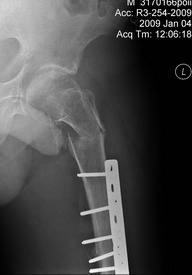

[Ortho] Перелом проксимального отдела бедра

АС> На снимке есть только дистальный отдел бедра, похоже, еще (или уже?) несросшийся на

АС> фоне DCS. Что за перелом проксимального бедра, пока информации нет.

Р-гр шейки

Имя     : Pochebyt 0901040002.jpg